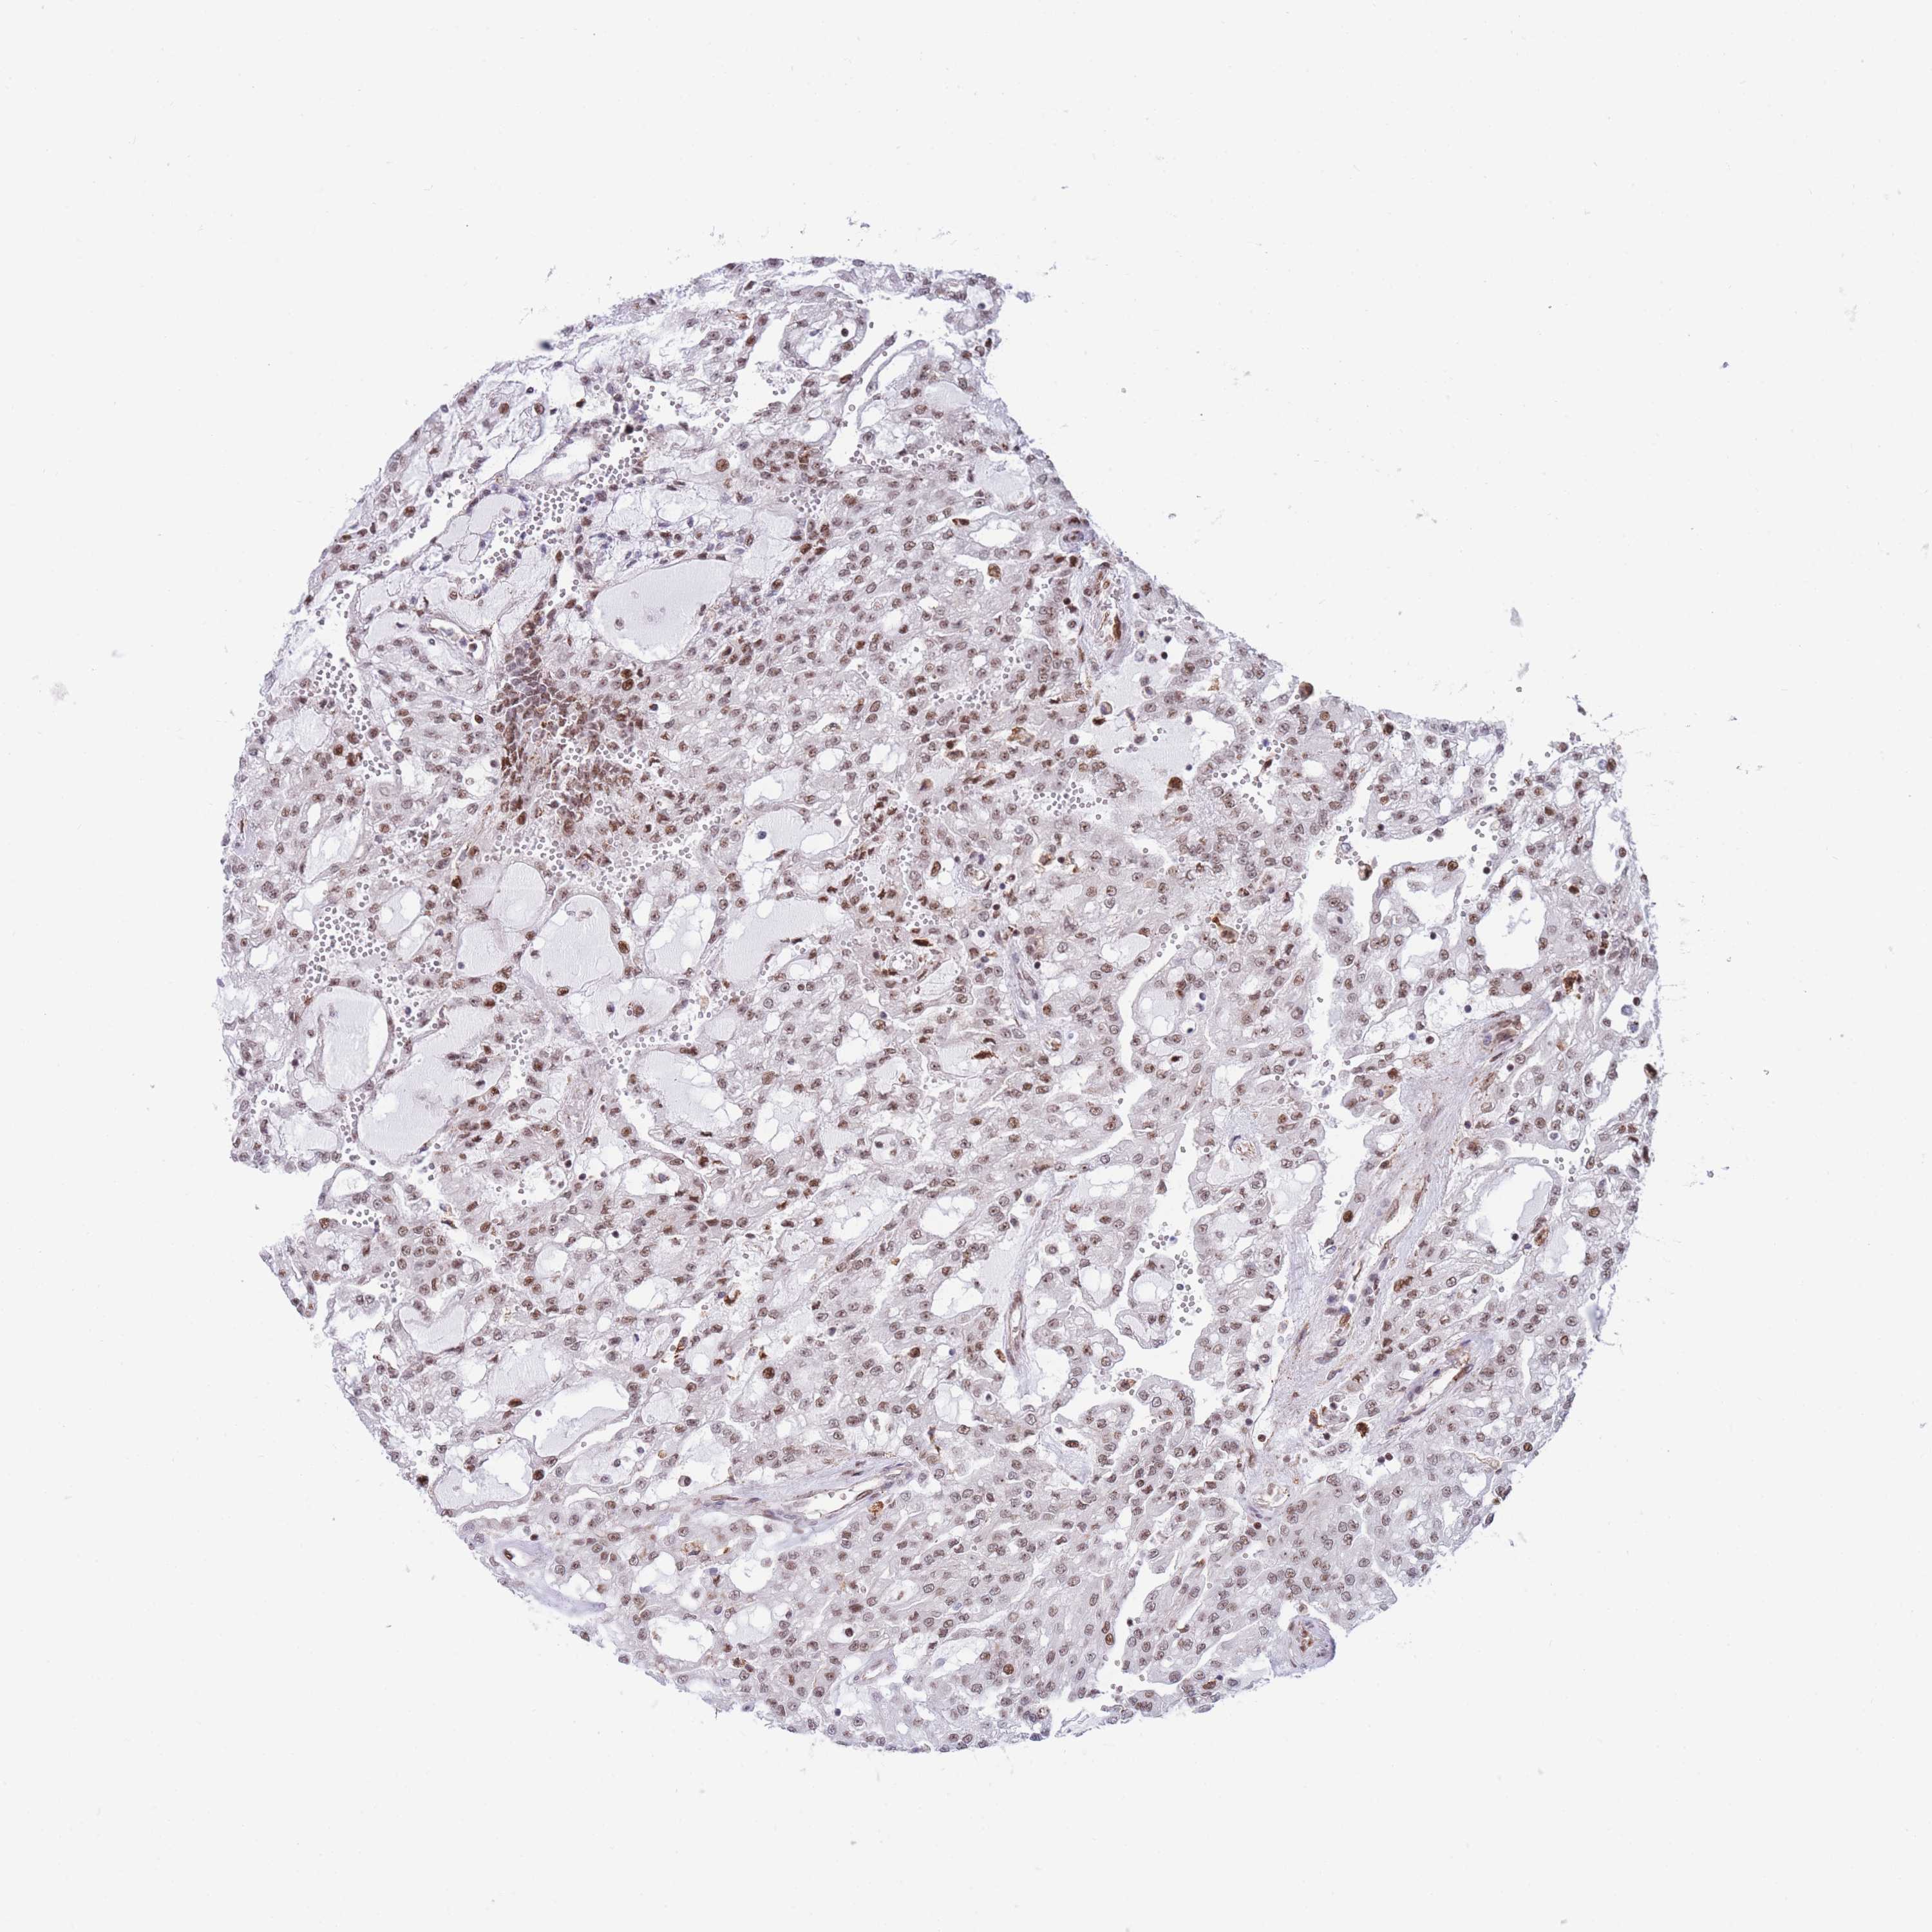

KIDNEY RENAL CLEAR CELL CARCINOMA (VALIDATION) - Interactive survival scatter ploti

The Survival Scatter plot shows the clinical status (i.e. dead or alive) for all individuals in the patient cohort, based on the same data that underlies the corresponding Kaplan-Meier plots. Patients that are alive at last time for follow-up are shown in blue and patients who have died during the study are shown in red.

The x-axis shows the expression levels (FPKM) of the investigated gene in the tumor tissue at the time of diagnosis. The y-axis shows the follow-up time after diagnosis (years). Both axes are complimented with kernel density curves demonstrating the data density over the axes. The top density plot shows the expression levels (FPKM) distribution among dead (red) and alive patients (blue). The right density plot shows the data density of the survived years of dead patients with high and low expression levels respectively, stratified using the cutoff indicated by the vertical dashed line through the Survival Scatter plot. This cutoff is automatically defined based on the FPKM cutoff that minimizes the p-score. The cutoff can be changed by dragging the vertical line or by entering a cutoff value in the square labeled "Current cut-off".

Under the Survival Scatter plot the p-score landscape (black curve; left axis) is shown together with dead median separation (red curve; right axis). Dead median separation is the difference in median mRNA expression between patients who have died with high and low expression, respectively. It is calculated as follows: median FPKM expression of dead patients with high expression - median FPKM expression of dead patients with low expression. This is intended to aid the user in visually exploring custom cutoffs and the associated p-scores and dead median separation.

Individual patient data is displayed and can be filtered by clicking on one or more of the category buttons on the top of the page. Categories describing expression level and patient information include: high, low, alive, dead, female, male and tumor stages. The scale of the x-axis can be toggled between linear and log-scale by clicking on the "x log" button. Mouse-over function shows TCGA ID, patient information and mRNA expression (FPKM) for each patient.

& Survival analysisi

Kaplan-Meier plots summarize results from analysis of correlation between mRNA expression level and patient survival. Patients were divided based on level of expression into one of the two groups "low" (under cut off) or "high" (over cut off). X-axis shows time for survival (years) and y-axis shows the probability of survival, where 1.0 corresponds to 100 percent.

DNAJC3 is not prognostic in Kidney Renal Clear Cell Carcinoma (validation)

: 42.28

Average pTPM 43.0

Number of samples 100